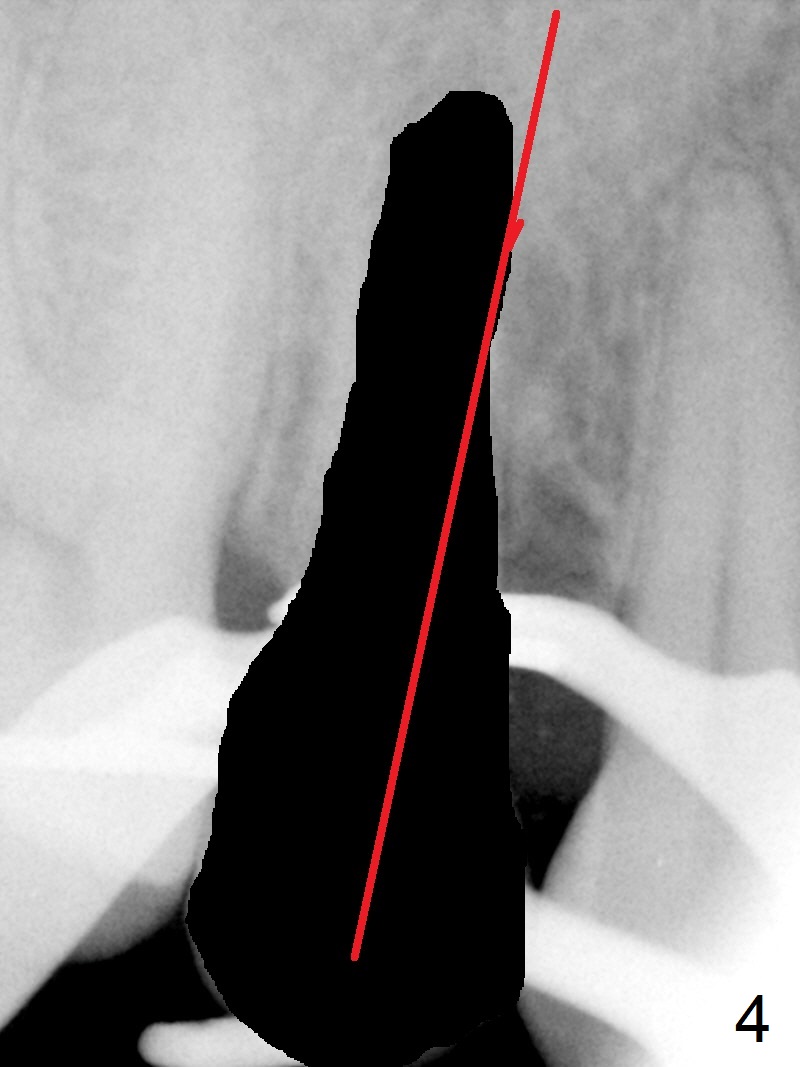

Seven years post RCT (Fig.1), the tooth #4 of a 65-year-old woman fractures subgingival palatally (Fig.2).  Since the root of the affected tooth is close to the tooth #3, osteotomy is established in the mesial slope of the socket (Fig.3).  Change the trajectory once the drill has penetrated the lamina dura of the socket (Fig.4).  The initial depth will be 20 mm for a 3.8x16 mm implant (Fig.5).